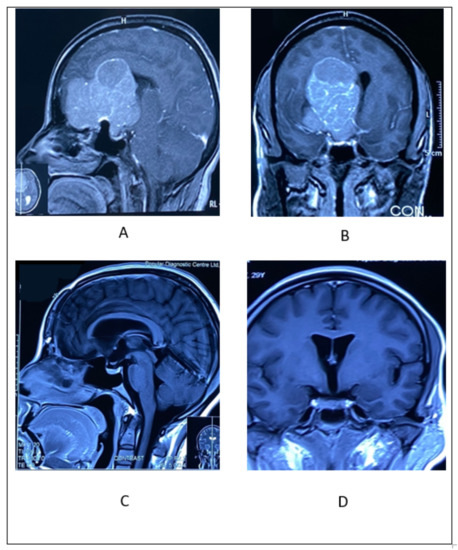

2.3.2. Illustrative Case 3

2.4.2. Illustrative Case 4